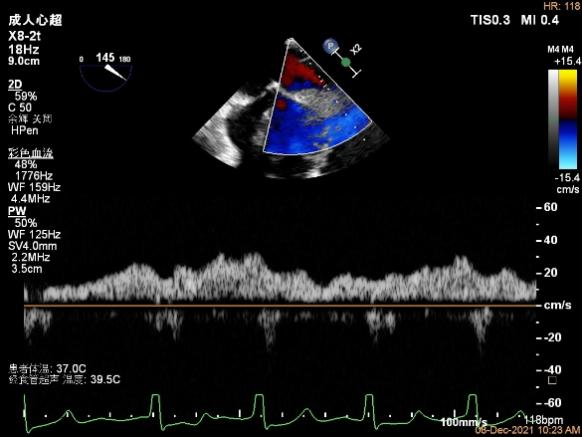

2D视图下trajectory

2D视图下开夹子

夹子关闭过程中,Color提示2区反流逐渐减少,残余反流位于夹子外侧

第一个夹子放置侯二尖瓣口平均跨瓣压差:4mmHg

肺静脉血流频谱恢复正向